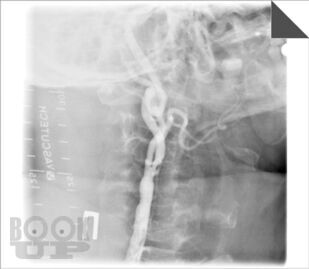

В пособии представлен не только хирургический раздел, но и анатомия кровообращения головного мозга и неврологическая симптоматика цереброваскулярных нарушений при атеросклеротических каротидных поражениях, поскольку каротидная хирургия неразрывно связана с этими аспектами. Приводится алгоритм обследования больных, охватывающий все современные методы нейровизуализации с указанием уровней доказательности, чувствительности и специфичности каждого из них. Особый акцент сделан на ценности ультразвуковых методов, которые наиболее доступны в клинической практике и достаточно информативны. При изложении лучевой семиотики для иллюстрации основных ангиоморфологических изменений даны эходопплерограммы, ангиограммы. Подробно описаны показания к хирургическому лечению, различные методы реконструкции сонных артерий.